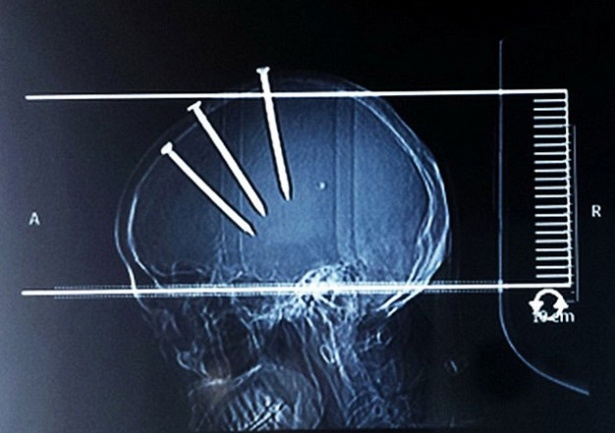

Çinli bir adam hastaneye getirildiğinde bu görüntüsü ile herkesi şaşırttı..

Çivilerin başları açıkça dışarıdan bile görünürken doktorlar Çinli adamın röntgenini çekti ve 3 koca çivi ile karşılaştı...

Hemen ameliyata alınan adamın başındaki çiviler teker teker çıkarıldı...

Çivilerin hepsi çıkarıldıktan sonra bir süre gözetim altında tutulan adamın sağlığı normale dönünce taburcu edildi...

Yapılan araştırmada Çinli adamın evini tamir ederken çivi tabancası ile yaralandığı ortaya çıktı...

Başına çakılan çivilerden 2 gün sonra haberdar olan adamın şimdi sağlığı gayet yerinde...